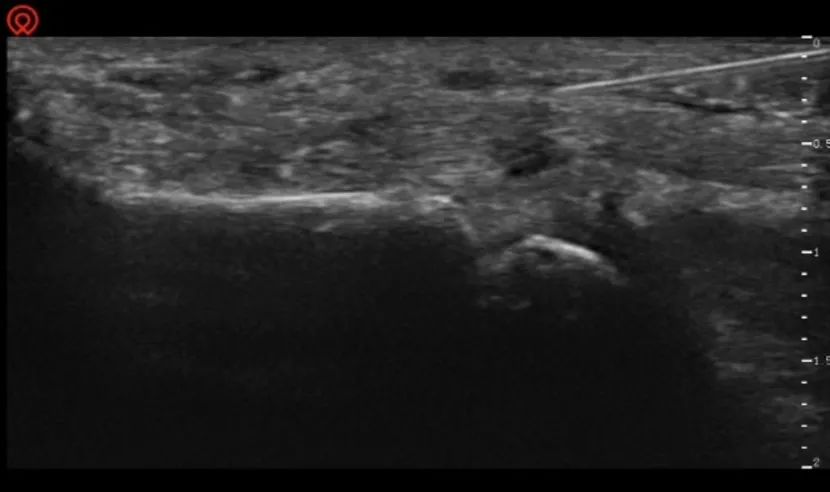

接诊的康复医学科副主任梁木荣副主任医师详细了解李阿姨的病情后,通过肌骨超声检查,清晰地看到李阿姨患指的情况:A1滑车腱鞘显著增厚,肌腱局部肿胀形成结节。诊断为拇指屈指肌腱狭窄性腱鞘炎,也就是俗称的“扳机指”。针对李阿姨的病情,梁木荣医师制定了精准的治疗方案。在超声实时引导下,他凭借精湛的技术,将穿刺针精准穿刺到病变腱鞘内注射抗炎药物,随后又进行了针刀松解。整个治疗过程精准且高效,最大限度地减少了对患指周围组织的损伤。治疗结束后,李阿姨当场活动拇指——弹响、疼痛和卡顿都消失了,“这种治疗方法真是太棒了!治疗过程短,几乎没有痛感,治疗后,我的手指很快就恢复了灵活。”如今,手指重获自由的李阿姨,又能轻松地拥抱孙儿,享受天伦之乐。

碰到这类问题,我院开展的肌骨超声介入技术能够巧妙地解决。肌骨超声介入技术是一项利用超声辅助下的介入性操作手段,能够清晰显示患者的关节、肌肉、肌腱、韧带和神经等结构,有助于医生把穿刺针准确定位到治疗位置,进行精准给药或治疗性操作,有效避免邻近重要结构损伤。超声下扳机指治疗,是在超声引导下将小针刀精准引导到卡压位置(肿胀滑车),进行精准切割、去除卡压,快速恢复功能。通常治疗一次即可解决问题,一般数分钟即可完成,创口仅一小针孔大小。